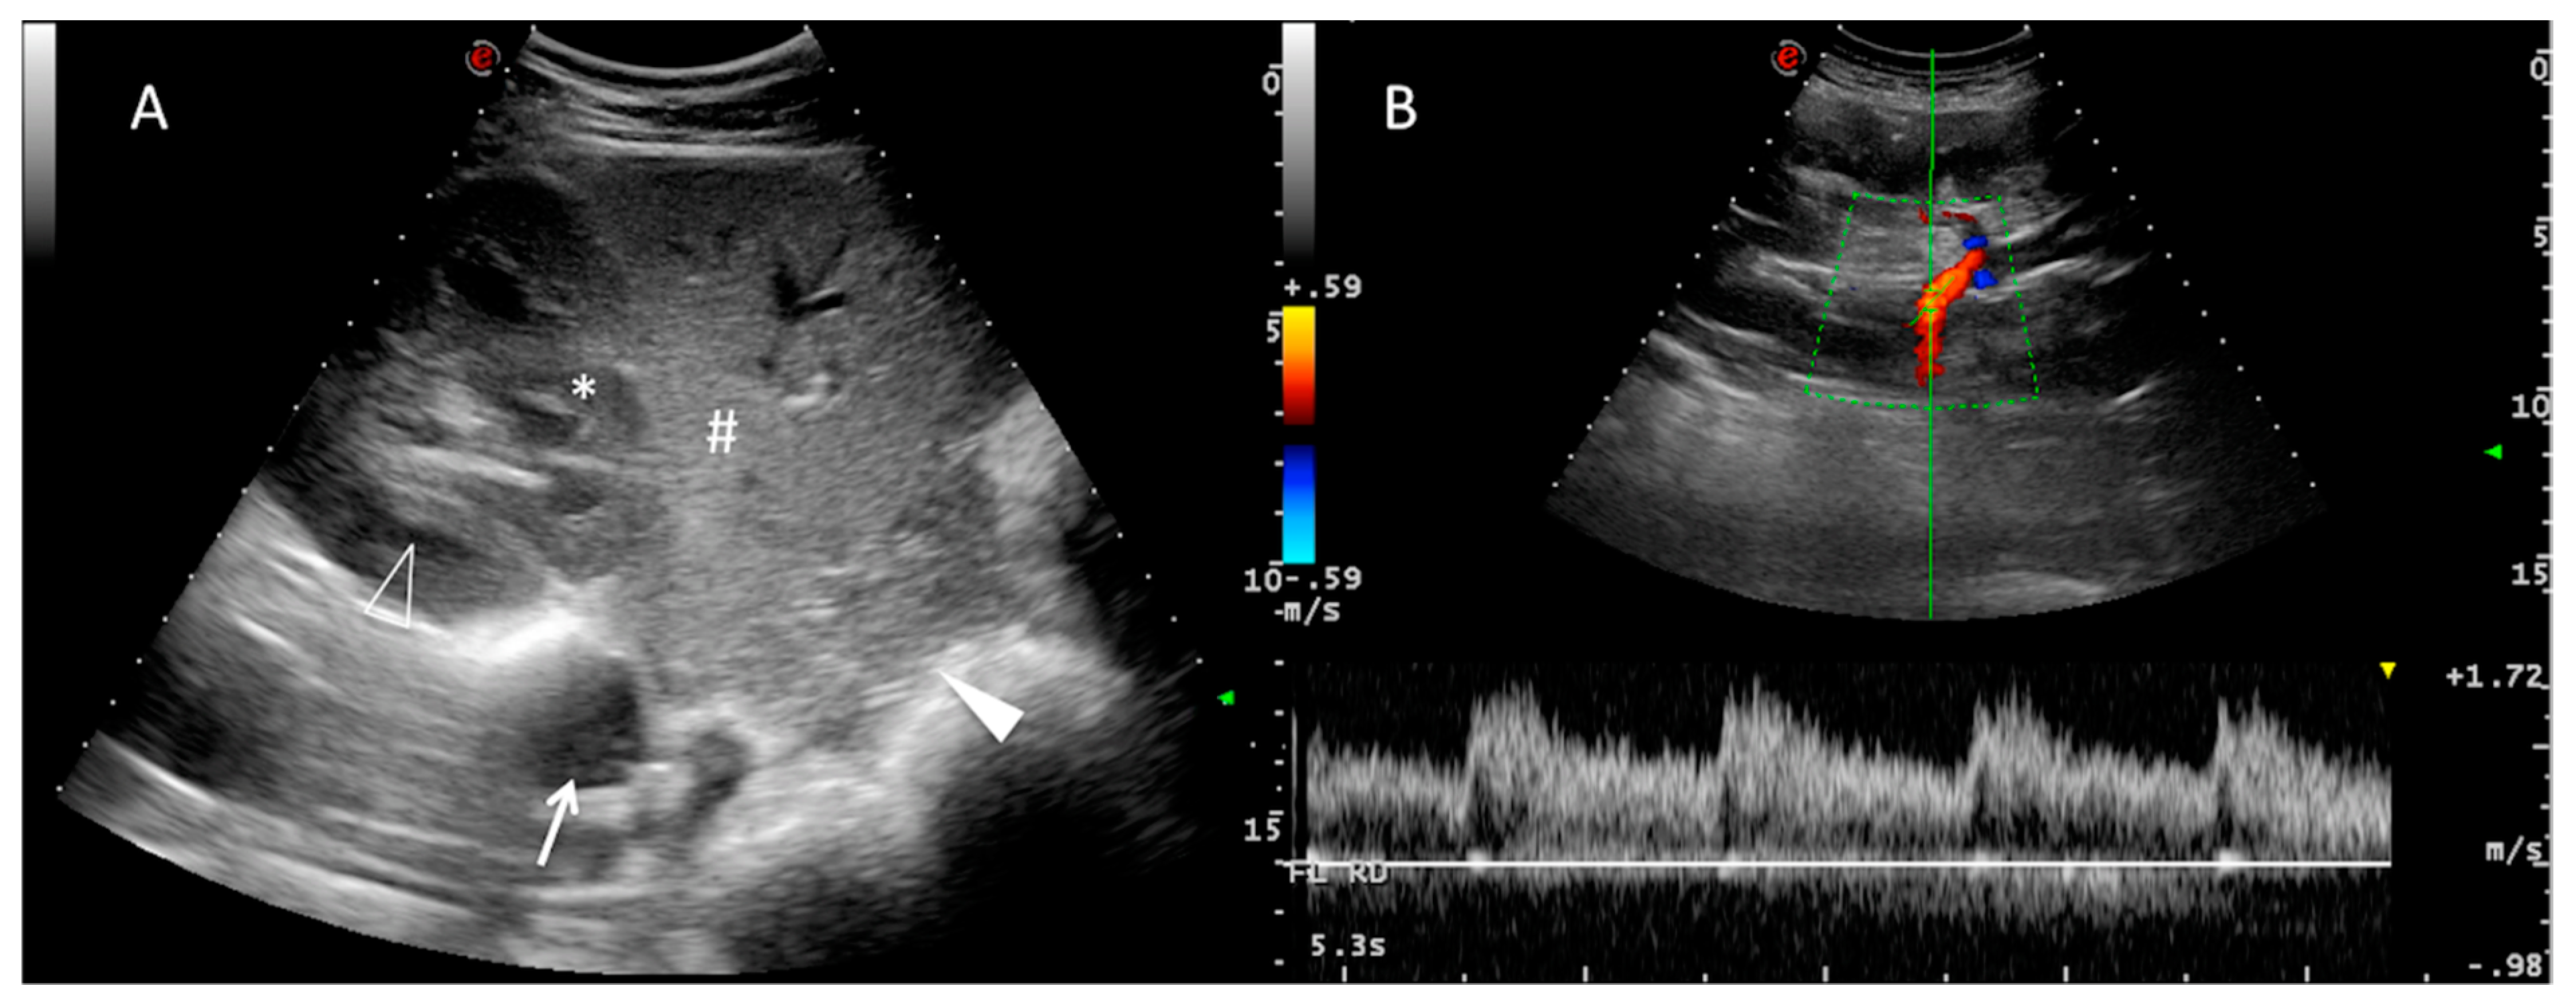

Figure 2.

Ultrasound images of the right kidney. (A): Transverse B-mode image of the right kidney in close contact with the liver for comparison of echogenicity. The renal cortex (*) is hypoechoic relative to the hepatic parenchyma (#). The renal medulla of one renal pyramid (hollow arrowhead), caudal vena cava (arrow) and pancreas (solid arrowhead) are also highlighted in this image. (B): Longitudinal B-mode image where the colour-coded Doppler demarcates the renal hilum and the main renal artery entering the kidney. A spectral waveform from the renal artery is visible with pulsed wave Doppler, with four consecutive and similar cardiac cycles visible over time (X-axis). The arterial flow (shown in red) towards the transducer, i.e., towards the kidney, confirms that it is the artery and not the renal vein.

When evaluating the vessel architecture by means of colour Doppler US, the main renal artery and its main tributaries (segmental arteries) were easily visible (Figure 2B). The distal interlobar and arcuate arteries could not be successfully mapped because of their small size and respiratory motion. Thus, only the main renal artery at the renal hilum and segmental arteries were included in the study.

The Doppler waveform of the renal artery and its main tributaries was characterized in all animals as a low-resistance profile [11] with a slow decrease in velocity once the peak systolic velocity was reached (Figure 2B). A small spectral window was visible under the blood waveform. No double systolic peak was detected, although a broad systolic peak was usually present, with slight generalized turbulence of the Doppler profile. The results of RI and PI are presented in Table 2. Age and weight did not influence the RI and PI. No differences were found between right and left kidney indices. On the basis of these results and applying the previous described formula, the upper cut-off values for RI and PI were 0.63 and 1.00 respectively.